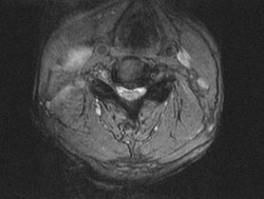

问题 男,65岁,颈部疼痛,双下肢无力3月余,请结合影像学检查,选出最可能的诊断 ( )

选项 A、小关节面综合征 B、椎管狭窄 C、脊膜瘤 D、脊膜膨出 E、脊髓空洞症

答案 B